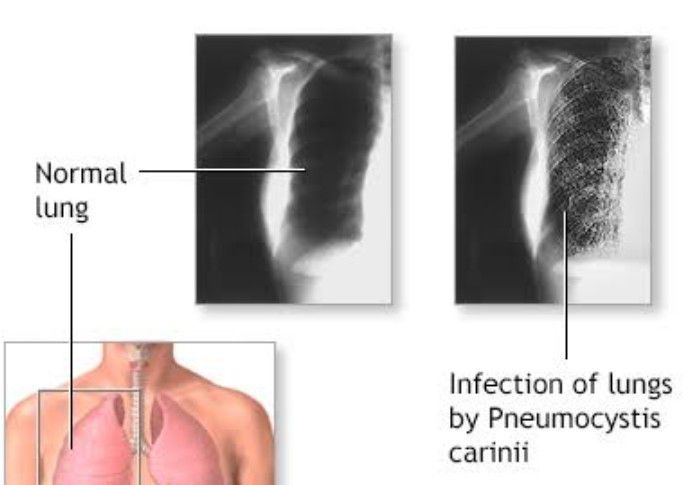

Pneumocystis pneumonia.

What is pneumocystis pneumonia? Pneumocystis pneumonia or PCP is a fungal infection in one or both lungs. It is common in people who have a weak immune system, such as people who have AIDS. The disease is less common in the U.S. than it used to be.